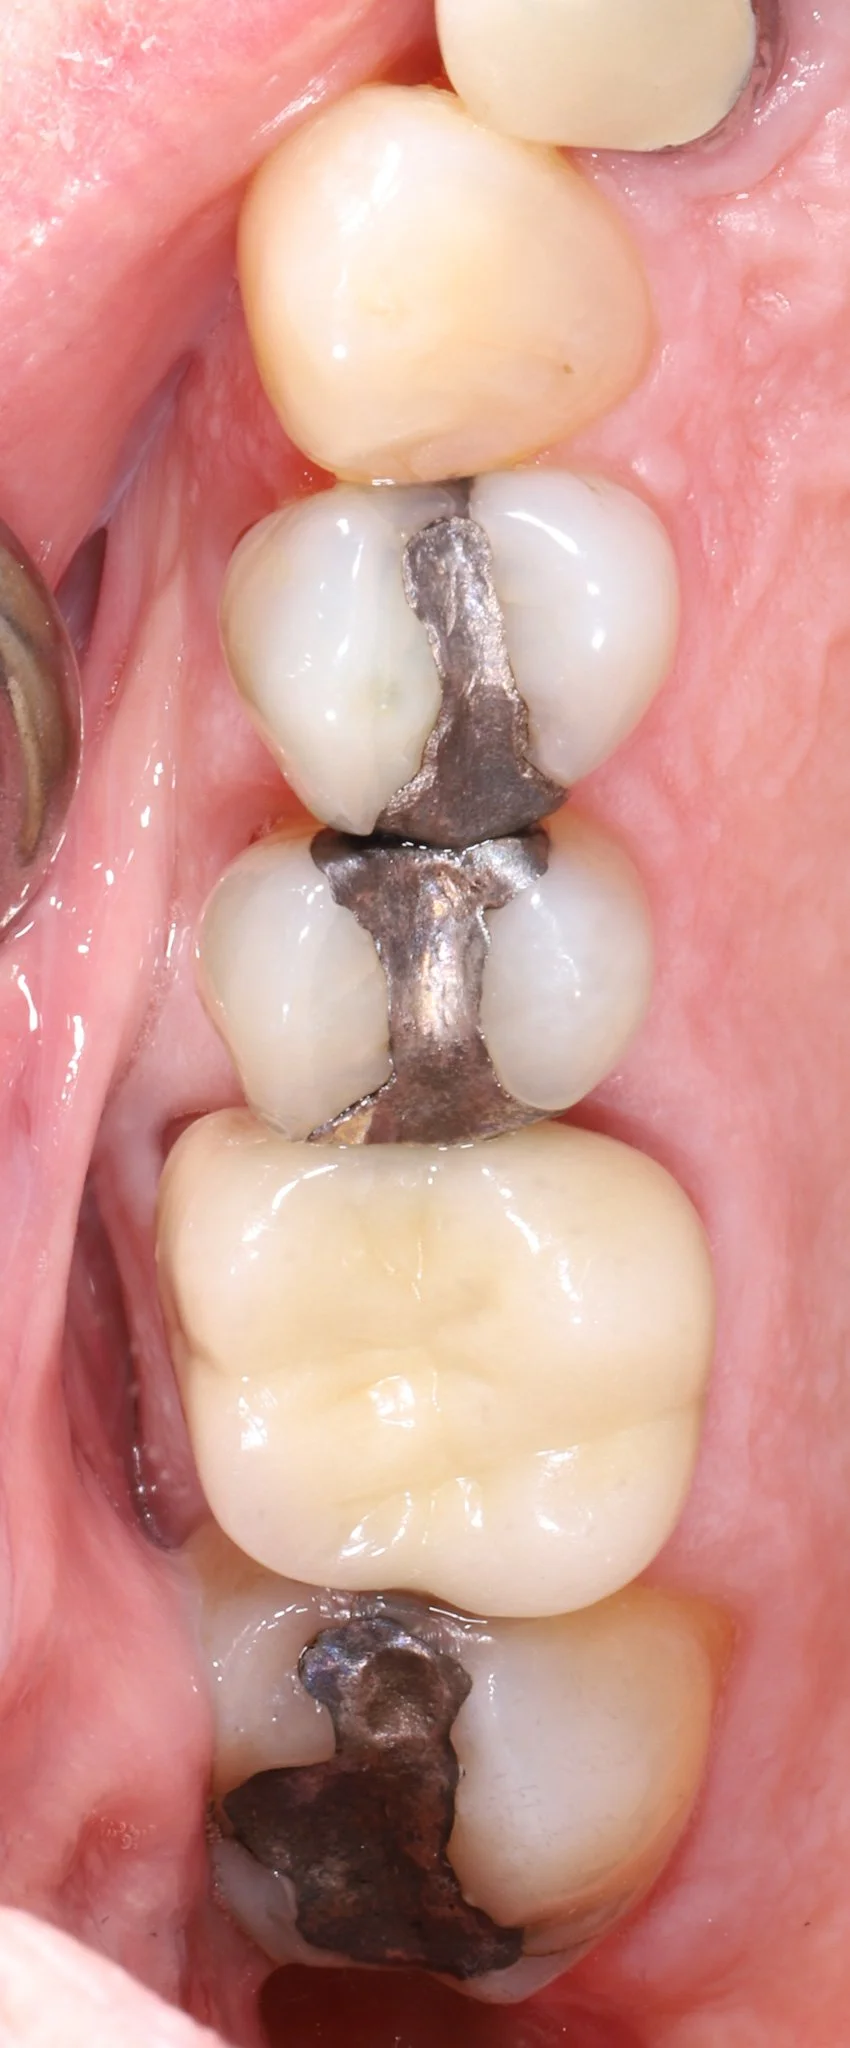

Close-up of molar teeth with signs of decay, leakage and cracks. Prior to restorative treatment.

Before: Leaking fillings, decay, cracked teeth

Close-up of molar teeth after restorations with bonded porcelain crowns showing optimal dental health.

After: New teeth blend seamlessly